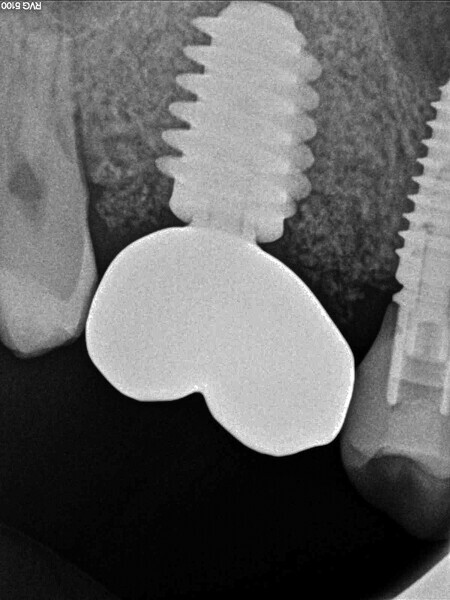

Digital workflow and application of PRF and ozone therapy in oral rehabilitation